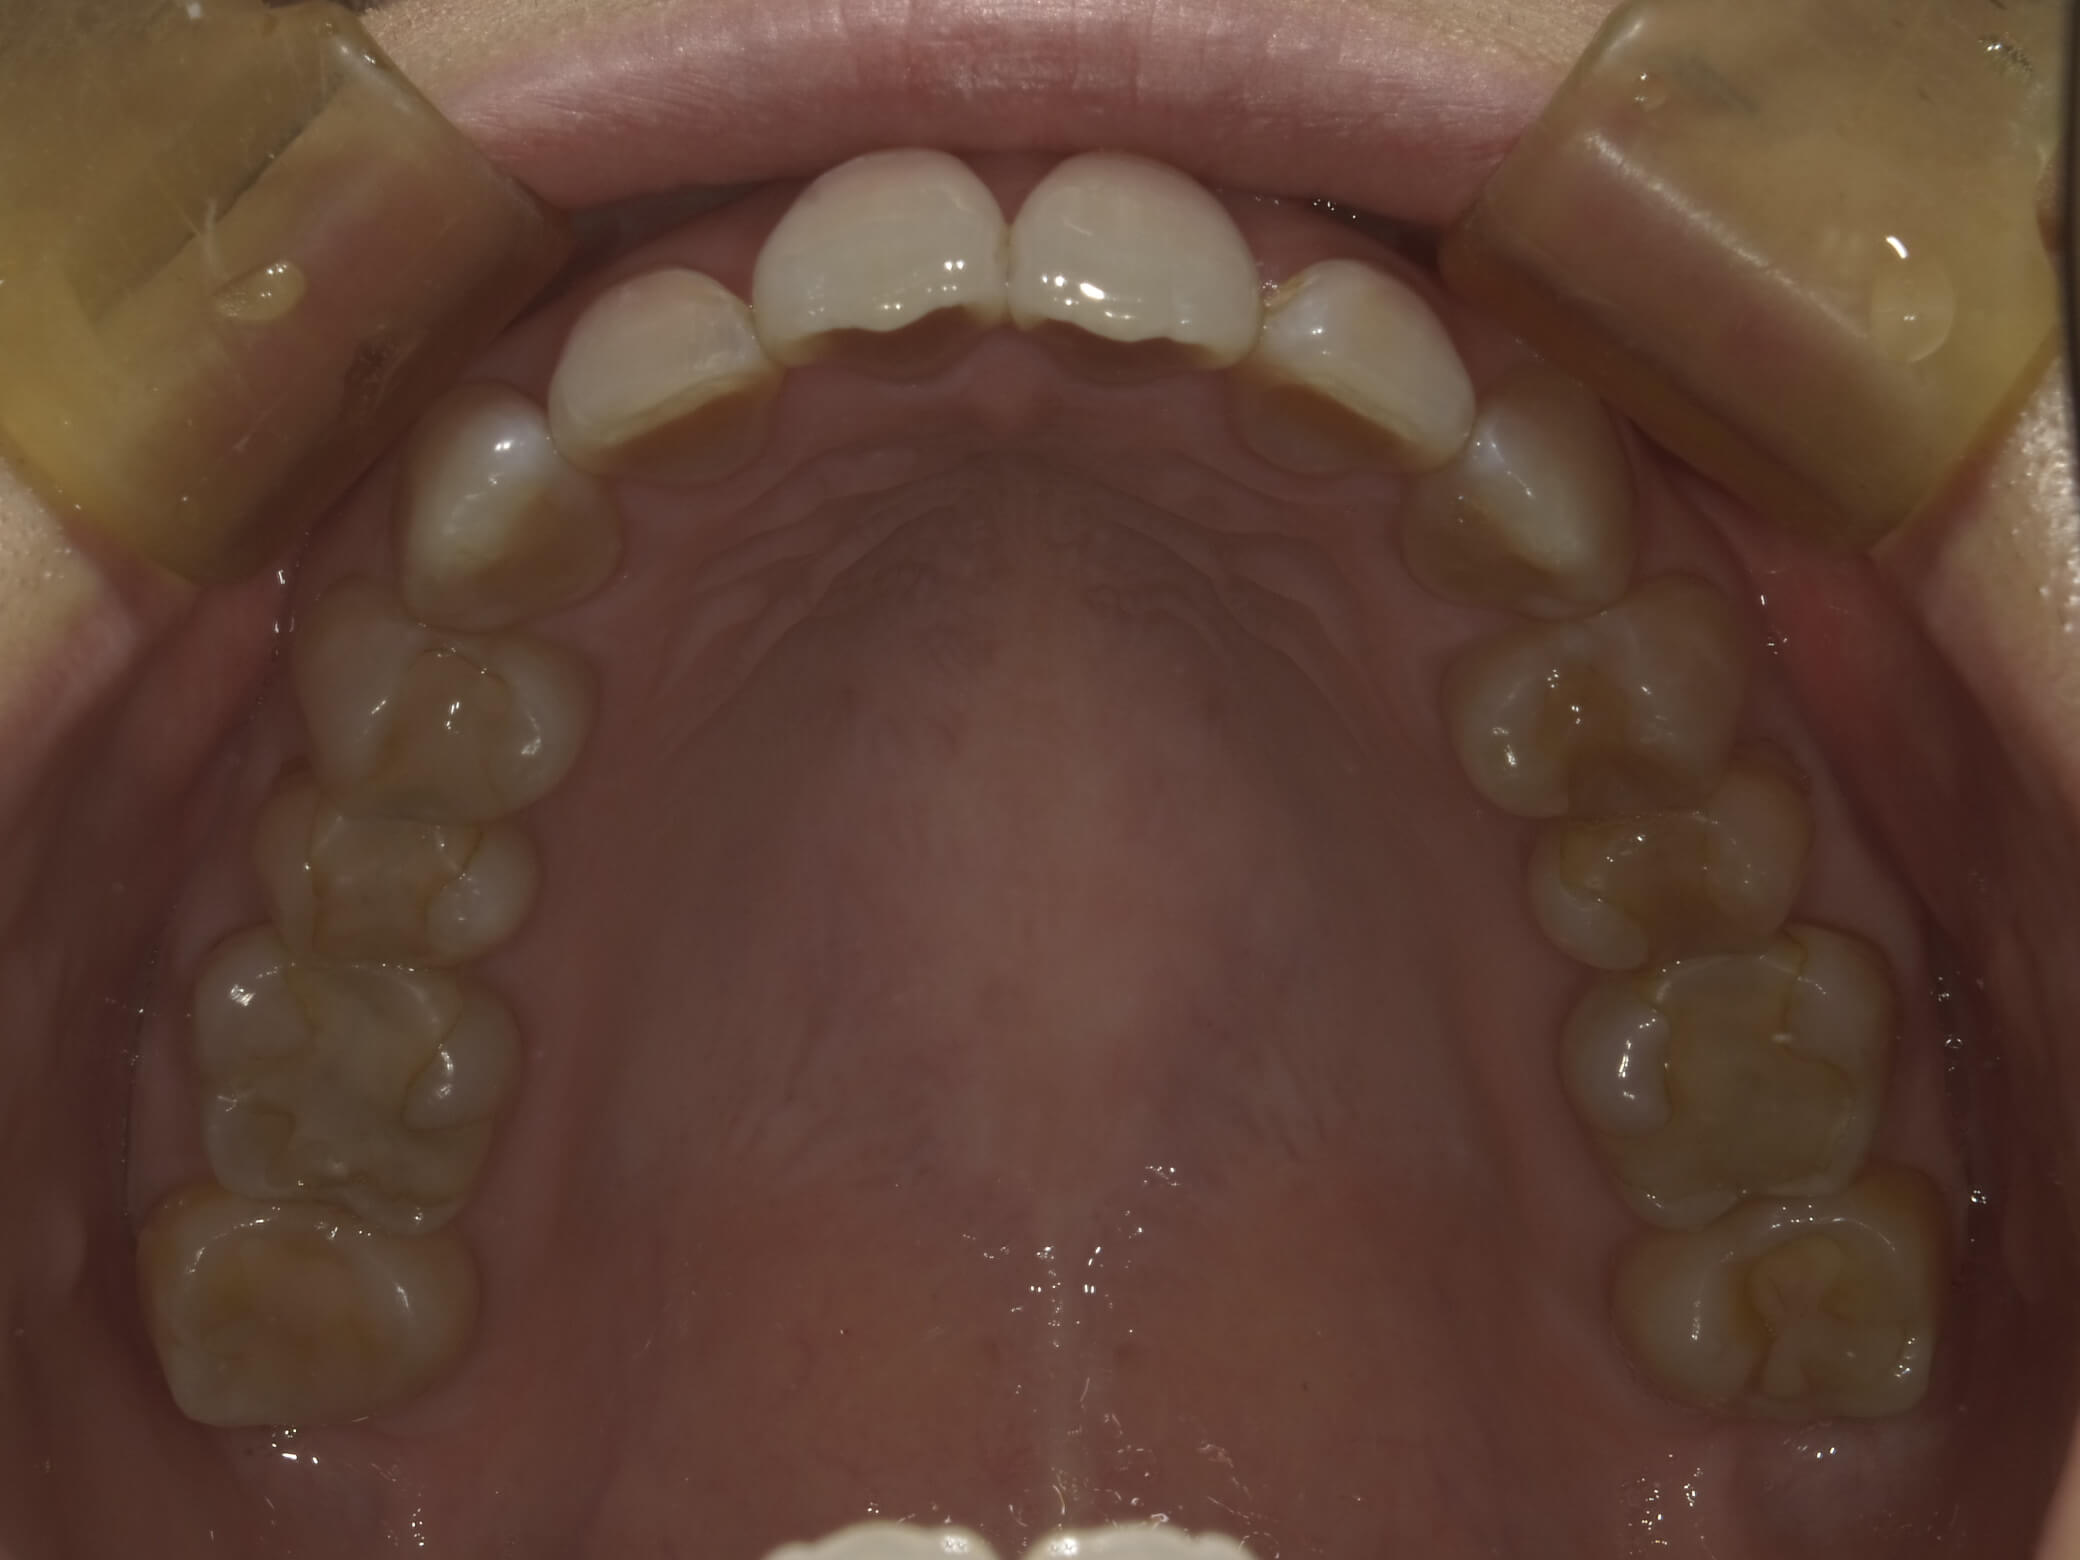

• 治療前

• 治療後